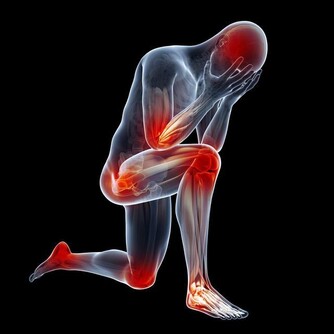

血管年輕了,身體的疾病也就少了,獲得也就更健康了。血液一旦變得粘稠,就會導致血栓、心肌梗死等等疾病,現在很多二三十歲的年輕人已經擁有三四十歲的血管,只是他們還不自知,一起來看看怎麼判斷血管是否還好嗎。

3、如果手掌很紅,指肚發紫,並且手腳經常是冷的麻的,這就不單單是血液粘稠的問題了,已經變成心腦血管病了,有可能心梗腦梗猝死,一定要馬上送醫院。